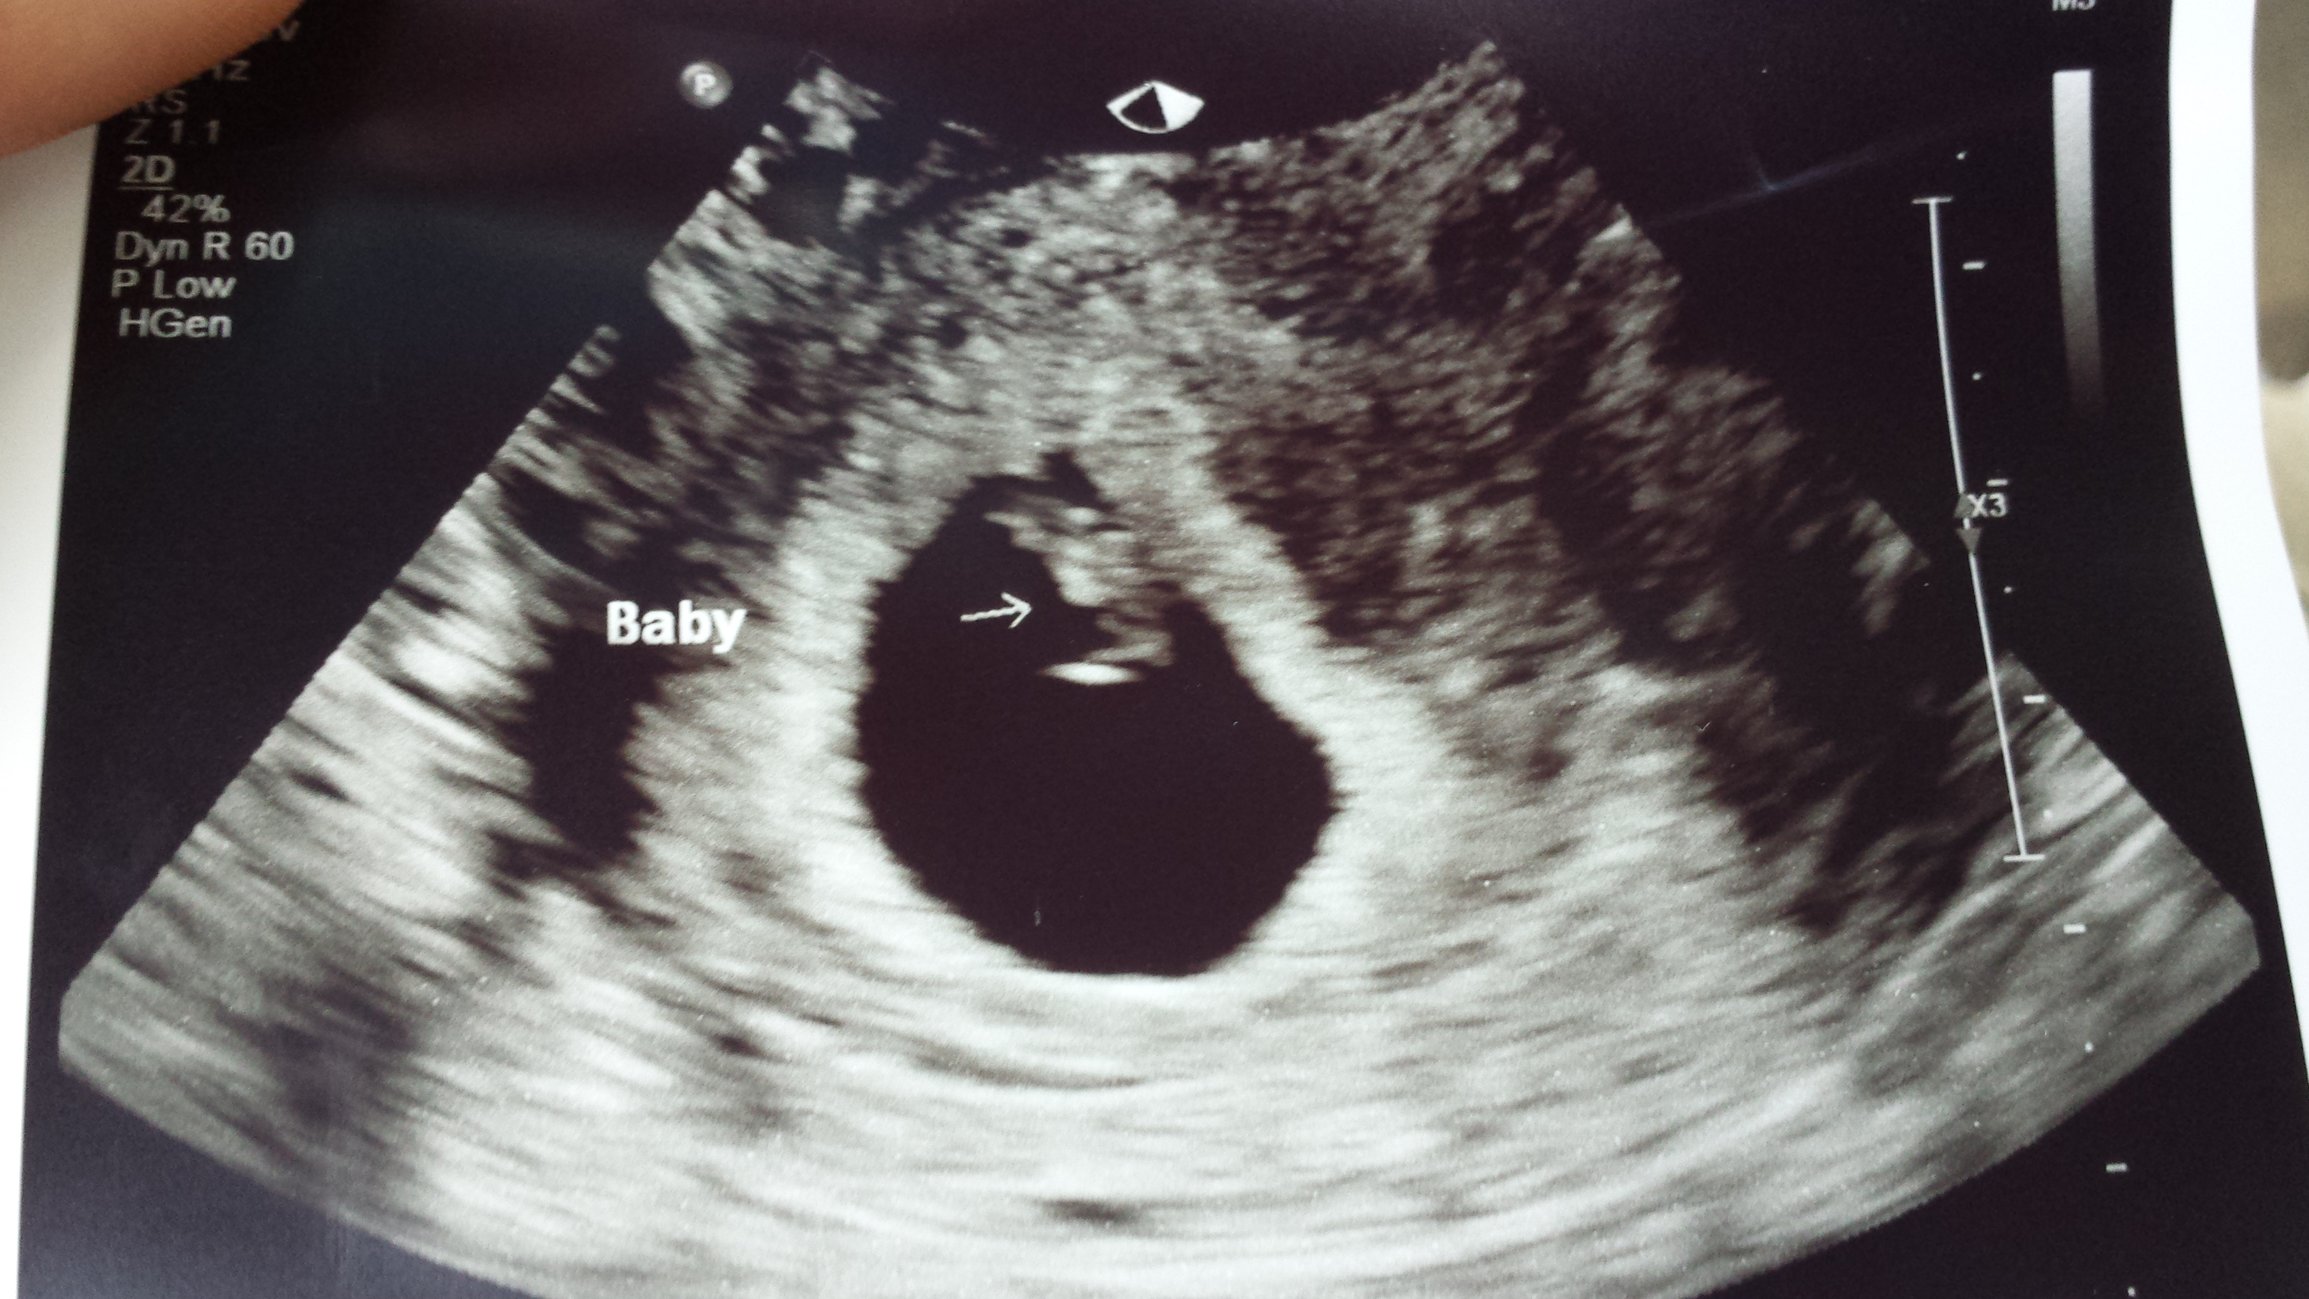

Our little nugget! Measuring a day ahead at 7w2d and a strong heartbeat of 151 bpm! I got to hear it and it was music to my ears!